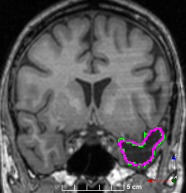

Refer to caption

(a)

(b)

(c)

(d)

(e)

(f)

Figure 3: Manual labels from Rater A (green) and Rater D, the model trained with PubFull + EpiPre + Pseudo (magenta). Errors caused by a (a) small resection, (b) blood clot in cavity and (c) brain shift; segmentations corresponding to the (d) 50th, (e) 75th and (f) 100th percentiles giving a DSC of 81.7, 86.5 and 93.8, respectively.